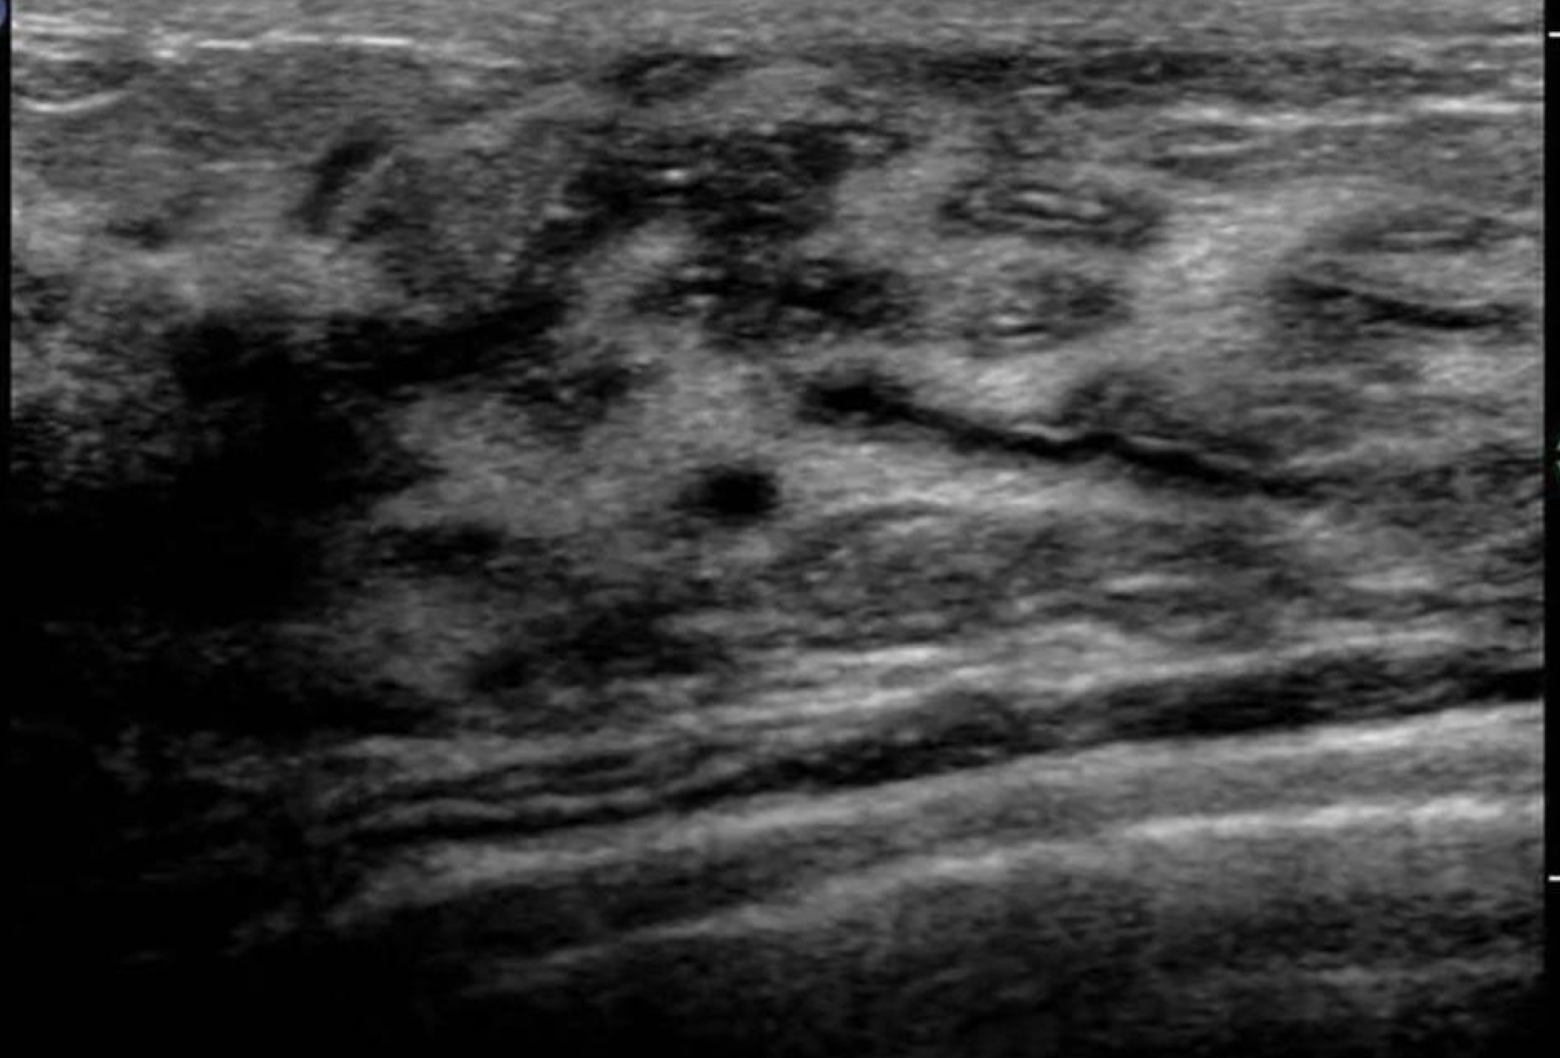

Mastitis

acute and chronic

begins in lactiferous ducts and spread via lymphatics or blood

occurs during lactation; inflammation of the breast

s/s: mastitis

enlarged, reddened, tender breast confined to one area of the breast